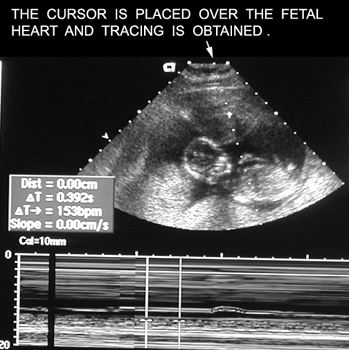

Fetal Heart |

|

Heart Trace |

|